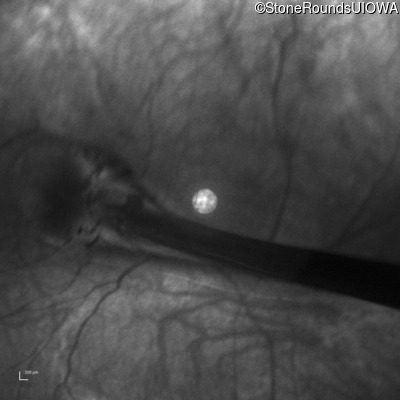

Infrared Fundus Photograph - Left - 20/300

Exemplar